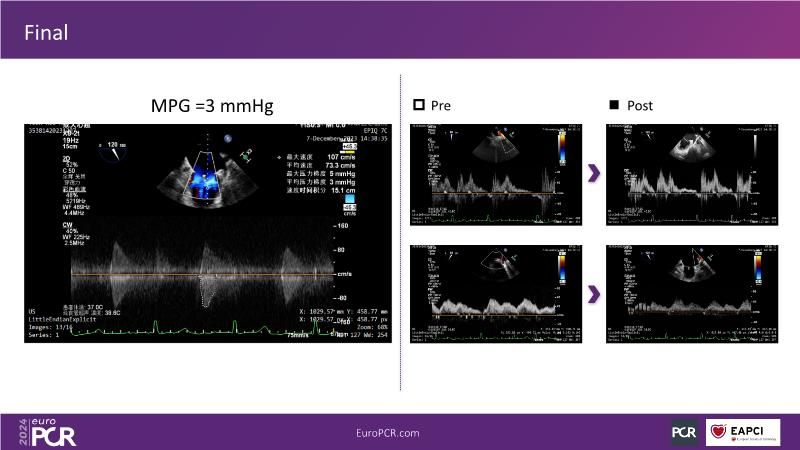

Watch this session to gain insights into the clinical evidence of mitral TEER therapy for the Asian population, learn techniques for implanting a MitraClip in patients with challenging anatomy, and understand how to use the four clip sizes for optimal outcomes. The session also covers educational aspects of clipping in dextrocardia, the benefits of reserve bending of the transseptal needle for tenting and puncture, new steering maneuvers for dextrocardia patients, and the importance of understanding anatomy and collaborating closely with the echo team for success.